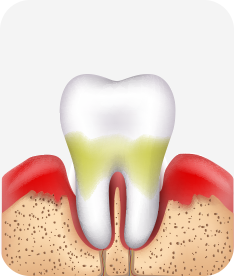

치주염 단계별 증상

건강한 상태

치아 주위의 잇몸이 핑크색을 띄며, 잇몸에서 피가 나지 않음.

스케일링을 6개월 ~ 1년 주기로 받고 올바른 칫솔질로 건강한 치주 조직을 유지

치은염 (초기~중기)

치아 주위의 잇몸이 붉게 부어 있으며, 칫솔질 등을 할 때 피가 남.

스케일링 주기의 조절이 필요할 수 있으며, 올바른 칫솔질을 시행하여야 함.

치주염 (중기~말기)

주기적으로 잇몸이 붓고 피가 나며, 욱씬하거나 우리한 통증이 나타남.

치주치료 및 정도에 따라 치주수술(잇몸수술)이 필요함. 향후 관리 정도에 따라 3~6개월 간격으로 내원하여 유지치료를 시행하여야 함.

치주염 (말기)

잇몸이 항상 부어 있으며, 이가

흔들리는 정도가 점점 심해짐.

치주치료가 필요하며, 정도에 따라 치아를 발치하여야 할 수 있음.